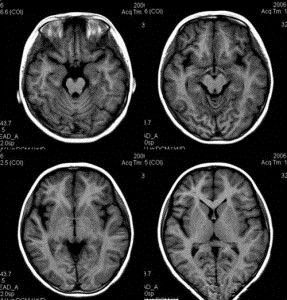

煙霧病一般頭部CT掃描可見梗死或出血性改變。梗死常為多發性的,以額、顳 、頂葉、枕葉 、基底節區、丘腦等處多見,半數病人可合併額葉萎縮。出血者可以是腦葉出血、基底節出血或蛛網膜下腔 出血,而高血壓引起的腦出血多位於基底節區。腦出血的患者也可同時發現梗死灶和(或)腦萎縮 。

6、CT掃描: 繼發腦梗死者可見血管分布相符的低密度區。蛛網膜 下腔出血者可見密度增高或血腫形成。